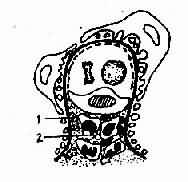

3.毛细血管内增殖性肾小球肾炎或内皮系膜性肾小球肾炎这是一种免疫复合物型肾小球明炎。发病初期,病变肾小球系膜细胞和毛细血管内皮细胞弥漫增殖,并有较多的白细胞浸润及严重的系膜水肿,称为渗出期。发病1-2周或更长的时间后,渗出成分大部分吸收,而以系膜细胞增殖为主,称为增殖期,这种系膜增殖现象可持续很长时间。电镜观察可见毛细血管基膜的上皮侧有“驼峰状”电子致密物沉积(图4-2-4)。荧光检查显示IgG和C3沿毛细血管壁呈粗颗粒状沉积。渗出期及增殖期的内皮系膜性肾小球肾炎有急性肾炎的临床表现。

图4-2-4 毛细血管内增殖性肾小球肾炎模式图。上皮细胞下电子致密物(免疫复合物)沉积,内皮细胞和系膜细胞增殖,白细胞浸润1.上皮下沉积物2.内皮细胞 3.白细胞 4.系膜细胞